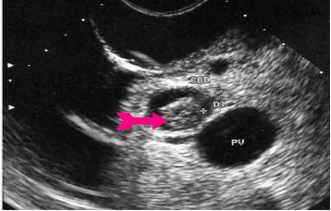

באולטרה-סאונד אפשר להדגים את דרכי המרה החוץ והתוך-כבדיות (תצלום 28.8).

| תצלום 28.8: סונר המראה הרחבה של דרכי המרה התוך כבדיות (מימין) וצינור המרה המשותף (משמאל). | |